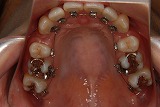

- 見えない矯正装置

見えない矯正装置09.12.04

見えない舌側(裏側)矯正装置を始められて、

3,4ヵ月過ぎて歯並びも全然変わってきているのに、